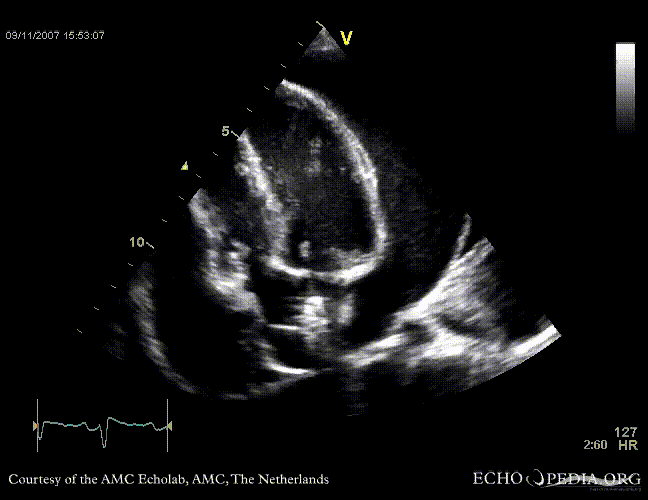

Tamponade

Courtesy of:

J. Vleugels, AMC, The Netherlands

tamponade 11